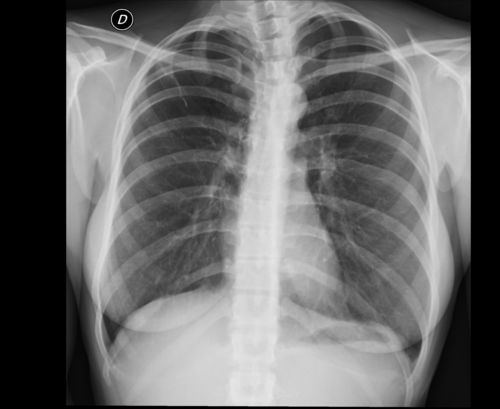

Добрый день! Очень нуждаемся в консультации. В конце августа 2025 в возрасте 7 месяцев ребенку сделали прививку БЦЖ. Ранее был медотвод по недоношенности (родилась в 30 недель). К ноябрю образовался большой гнойник, обратились к фтизиатру, было назначено лечение примочками с рифампицином с димексидом и дисцилированной водой в пропорции 20/80Показать полностью...

Я не вфитизиатр, но ответить могу. К сожалению вся эта история с заживлением может длиться долго, иногда до 1,5 лет. Фтизиатр тут сделать ничего не сможет. Нужно мросто ждать. Антибиотик, примочки все здесь правильно. Но процесс будетПоказать полностью...